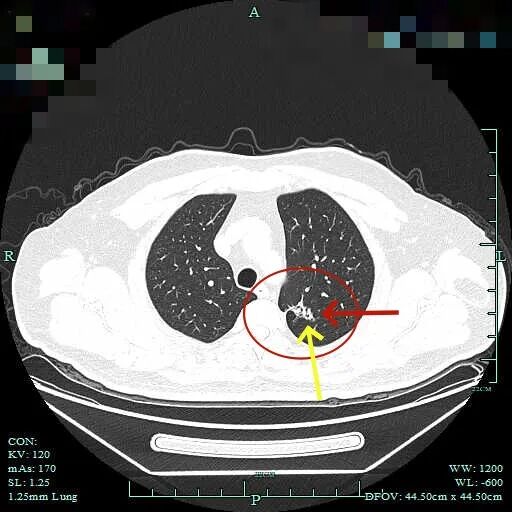

先看2022年12月时的影像:

这个片子质量较差,雪花点很多,清晰度不够。但这个病灶整体轮廓较清,密度不纯,贴近主动脉与叶间裂,灶内有细小空泡征,是要高度怀疑恶性,短期抗炎治疗后复查若无吸收好转,宜及时手术为稳妥。